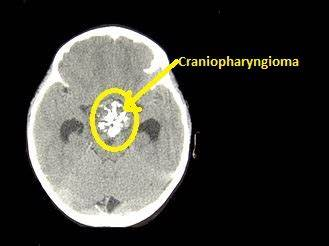

什么是顱咽管瘤?

顱咽管瘤是兒童和成人中蝶鞍和鞍旁區(qū)的良性上皮腫瘤,可能由 Rathke 囊和顱咽管的外胚層衍生上皮細胞殘余物的腫瘤轉化引起。

顱咽管瘤主要有三個臨床癥狀:

1.   1、顱內壓力增高引起的頭痛,嚴重時可伴有嘔吐。

2.   2、視力減退,可發(fā)生一眼或雙眼。

3.   3、內分泌功能障礙,因垂體生長激素的缺乏導致兒童生長發(fā)育遲緩,體格矮小但身體各部大小的比例正常。